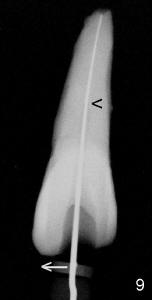

The tooth #8 of a 61-year-old man has obliterated canal probably due to trauma (Fig.1,2 (lateral view)). Initial access shows that the labial portion of the recessed pulpal horn (brown, < in Fig.3 (occlusal view) is not fully exposed, while that the most lingual aspect of the incisal edge (between **) has been removed. Further access appears to be necessary to expose the obliterated pulpal chamber (Fig.7 <) and more of the incisal edge has been violated ( between **). With good exposure, the canal is easily found around the arrowhead (<) in Fig.7. Laterally, the initial file: C6 is straight and slightly labial to the incisal edge (Fig.6). But it is somewhat bent in the front view (Fig.5). After enlargement of the coronal canal with Gates-Glidden files #2 and 3 (Fig.9<), #20 file appears to move distally (<-) and is straighter than the file in Fig.5. Laterally, the #20 file remains without much tension and around the incisal edge (Fig.10). Fig.11 shows occlusal view of the access after application of Gates-Glidden files. Before rotary files, the access is enlarged further both labially and lingually with diamond/carbide endo access burs (Fig.15). Fig.13,14 show 40/.04 file in the canal free without strain. The file seems to move distally further (Fig.13 <-).